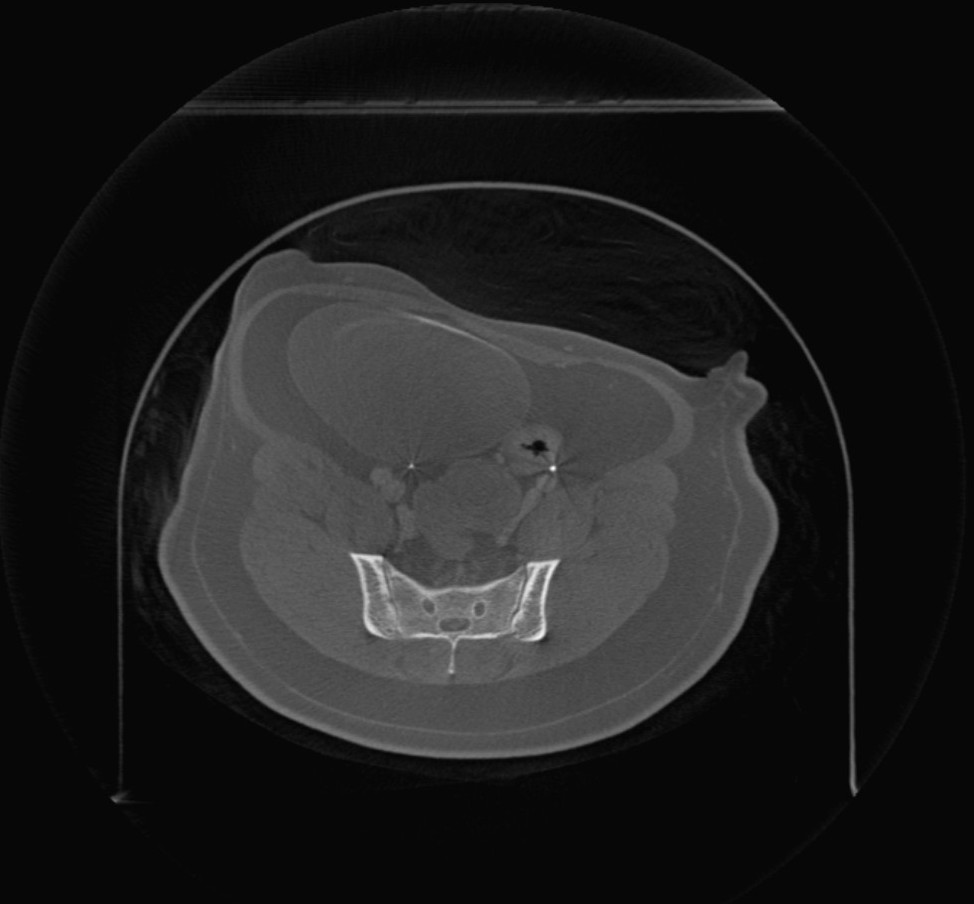

Beim Öffnen volumetrischer DICOM-Bilder im Viewer (CT- und MR-Modus) steht in der oberen Symbolleiste ein zusätzliches Menü mit dem Titel Bildebenen zur Verfügung. Ändern Sie die Ausrichtung des Bildes, indem Sie eine der drei verfügbaren Ebenen auswählen (Axial, Koronal und Sagittal).

Die gewählte Ebene beeinflusst die Position und Ausrichtung der CT-/MR-Schnitte sowie deren Rekonstruktion auf der 2D-Ebene.